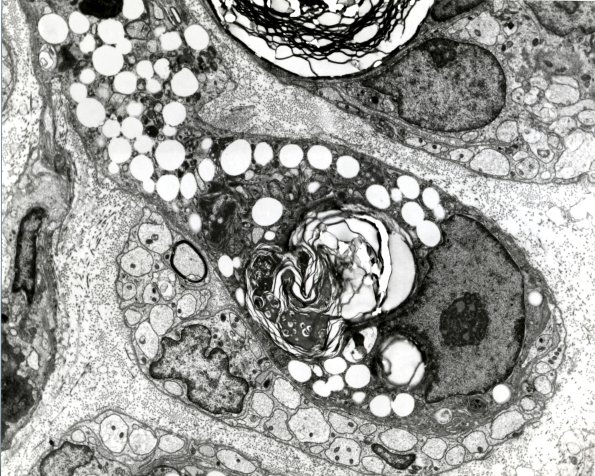

Washington University Experience | PERIPHERAL NEUROPATHY | 4 AXONAL DEGENERATION | 4 Macrophages | 4D2 Case 15 EM 4 - Copy

Higher magnification of image #4D1. (electron micrograph)